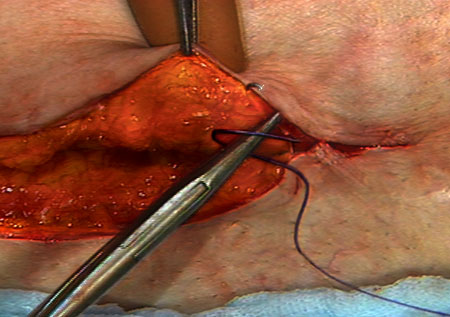

Purse String

A continuous stitch paralleling the edges of a circular wound. The wound edges are inverted when tied. Commonly used to close circular wounds, such as hernia or an appendiceal stump